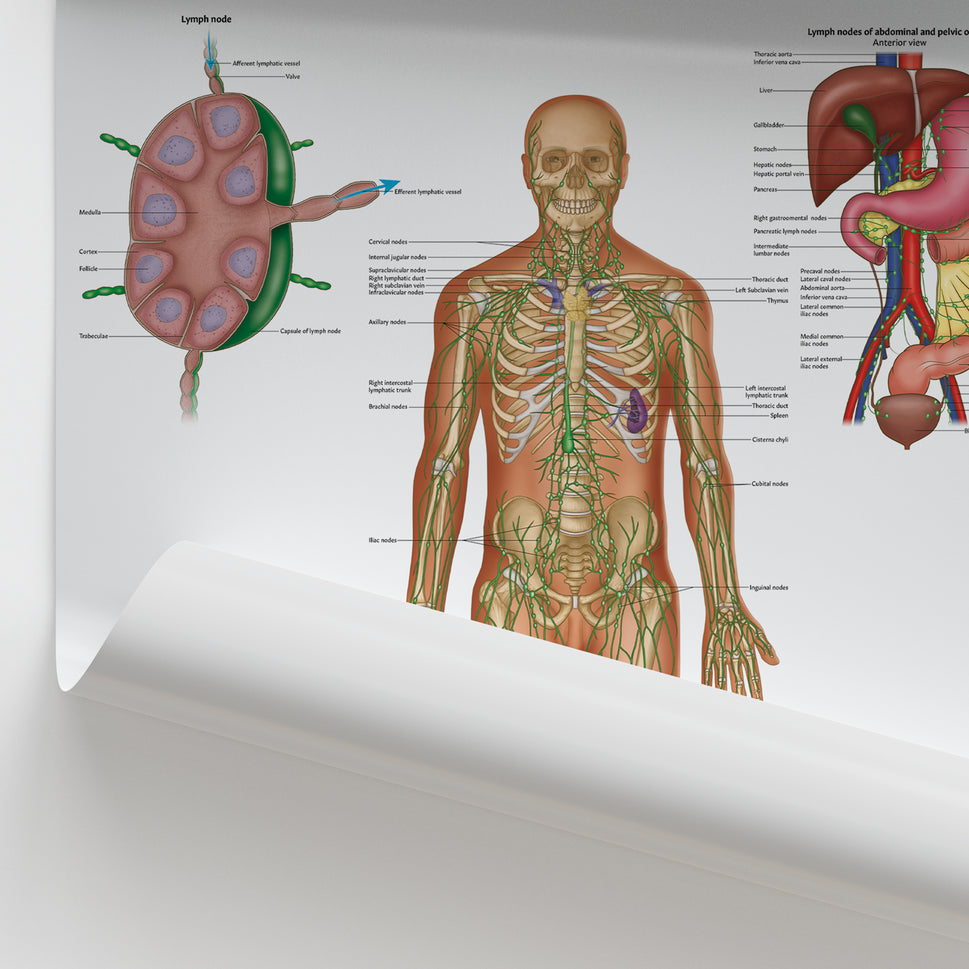

Enhance medical education with our collection of digestive system anatomical models including the stomach, liver, gallbladder, pancreas & colon models. Discover the anatomy of healthy organs as well as common gastrointestinal diseases such as stomach ulcers, gallstones and liver cirrhosis. Our digestive system anatomy posters are ideal for study and patient education.

At AnatomyStuff we stock a diverse range of digestive system anatomical models to suit your training needs. From budget models and affordable medical education posters to highly advanced 3D printed bowel models, you can transform medical training and patient education. As well as our own exclusive collection, we are proud resellers of 3B Scientific, Anatomy Lab, Denoyer-Geppert Science Company, ESP Models, Erler Zimmer and GPI Anatomicals. Explore our exclusive collection of digestive system anatomy charts, posters, fine art prints and digital anatomy study guides. Discover the anatomy of key organs like the liver, stomach, pancreas and bowel as well as the pathophysiology of common conditions like peptic ulcer disease, coeliac disease, IBD and much more. We have anatomy posters suitable for school children all the way up to medical degree level. From a liver anatomy poster to a digital study guide all about common GI disorders, find exactly what you need right here to enhance medical training and patient education.